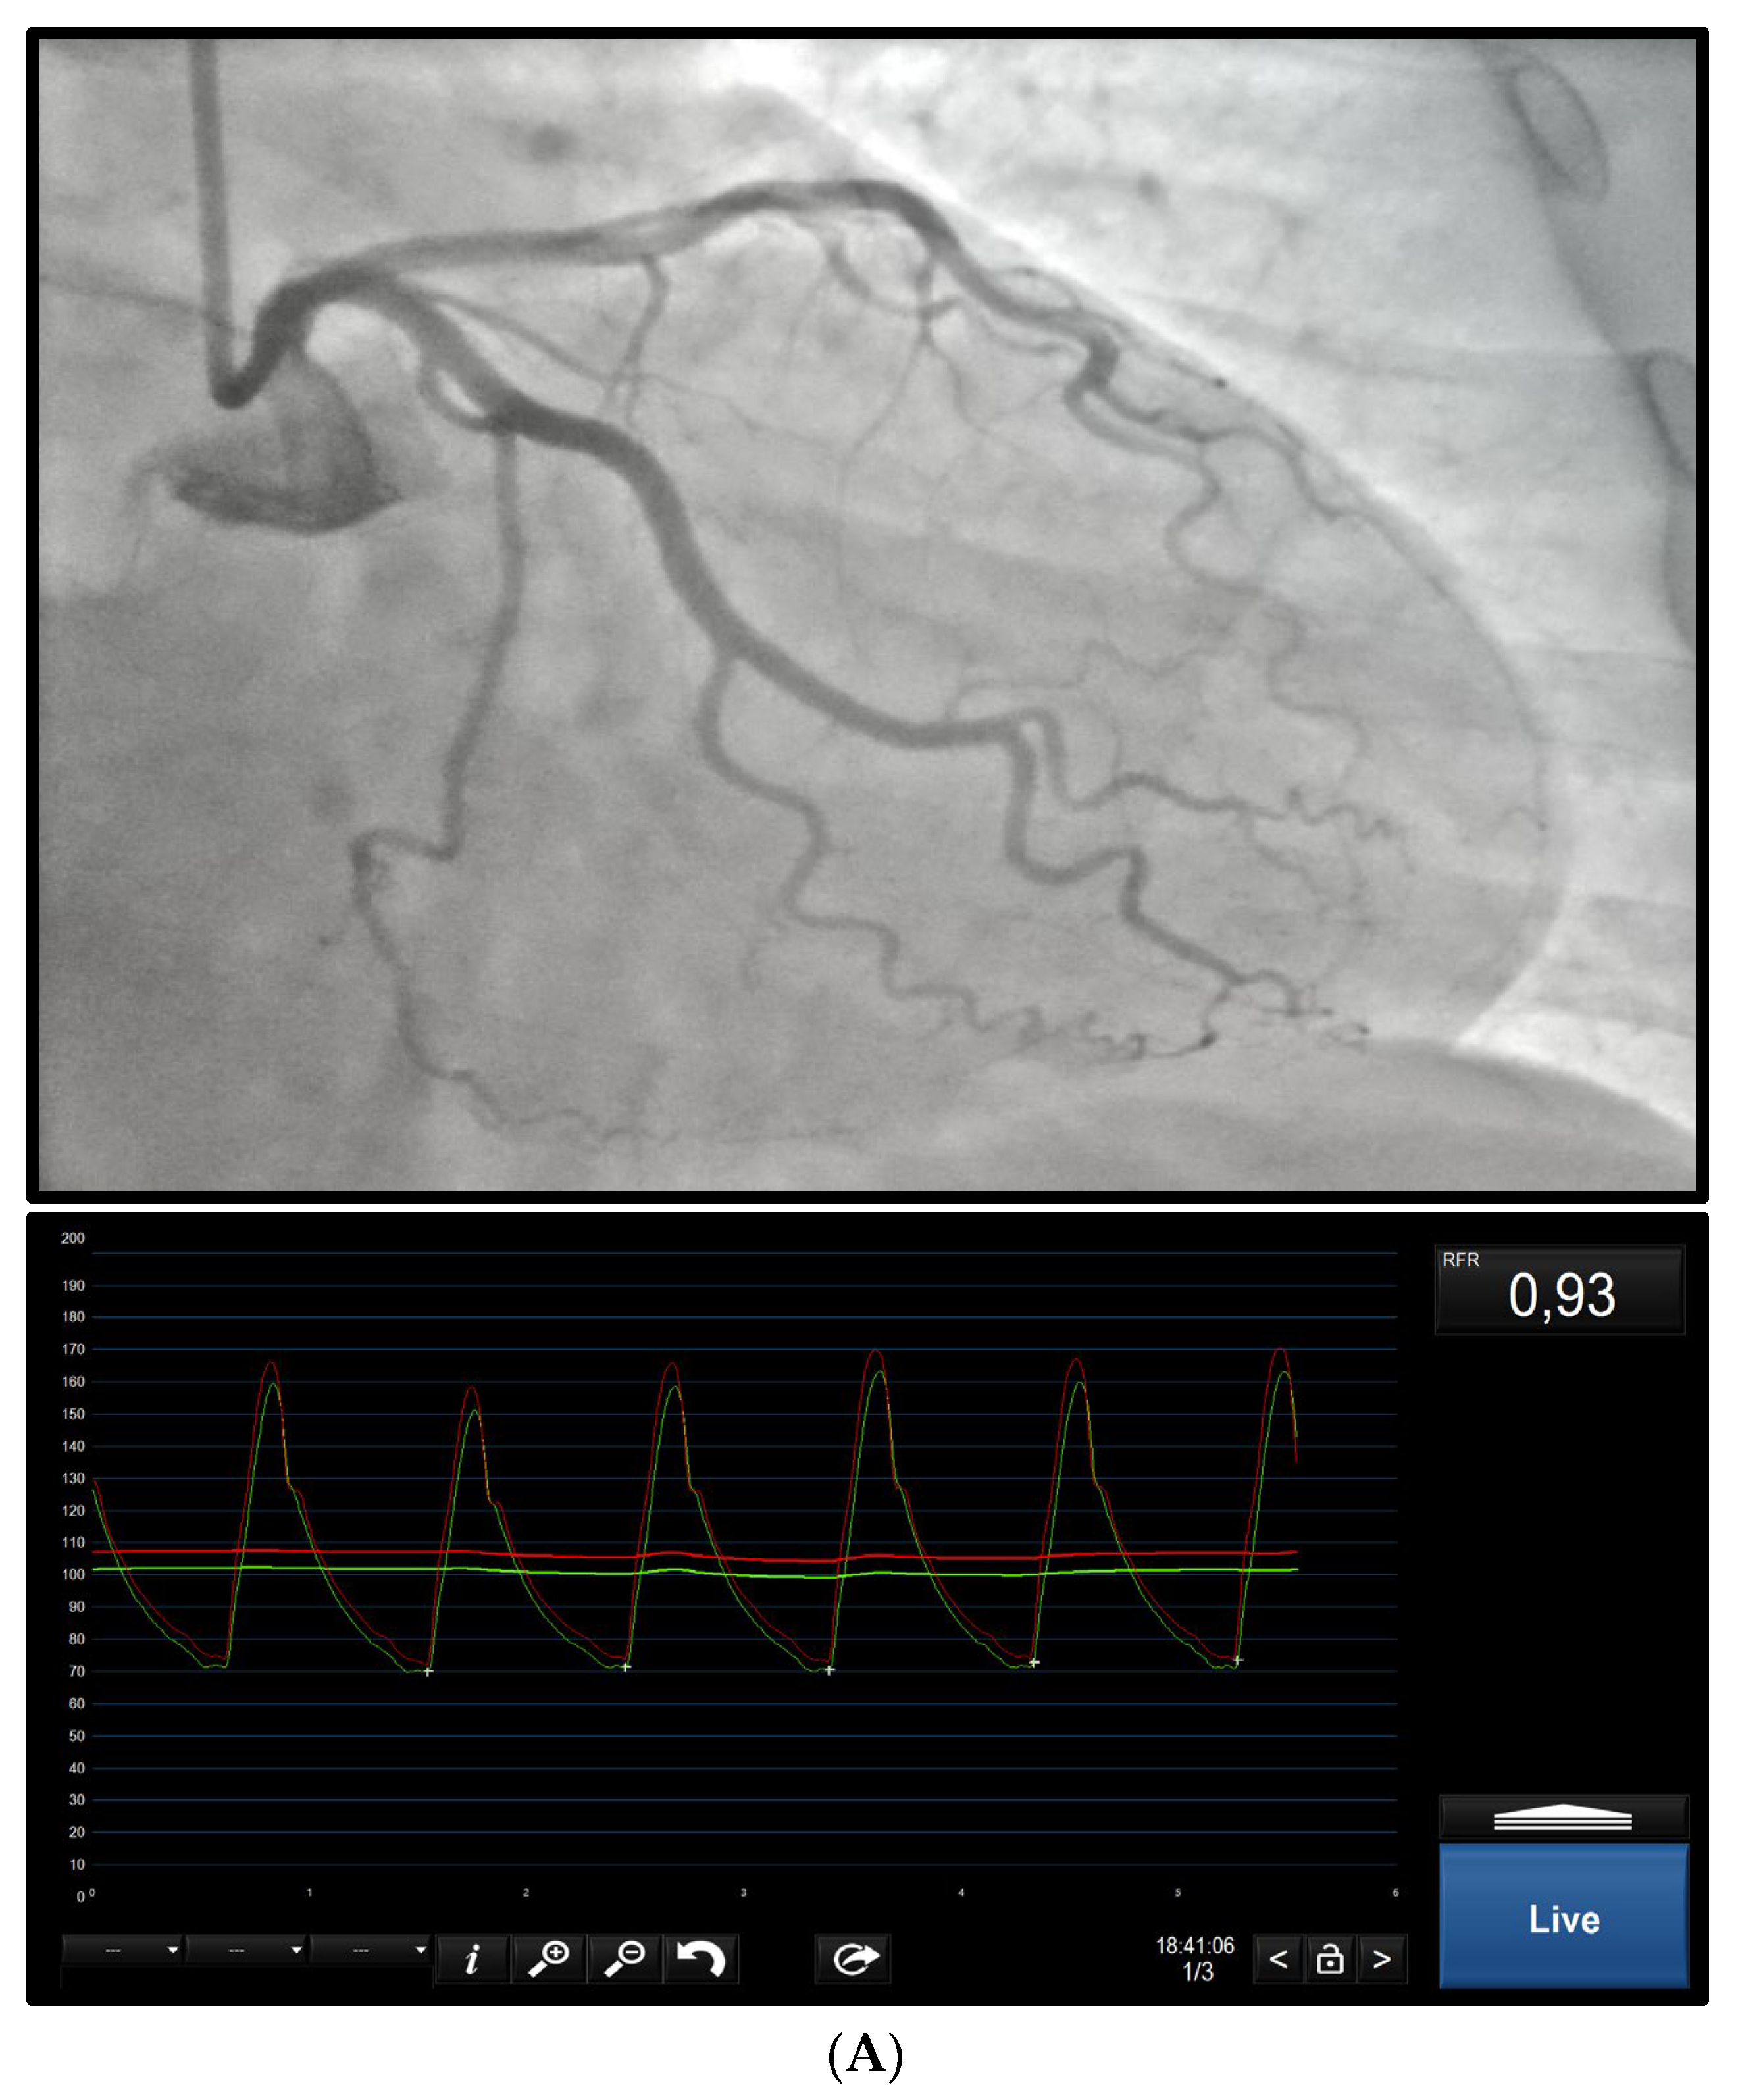

2. Epicardial Disease

2.1. Diagnosis

2.2. Post-PCI Assessment